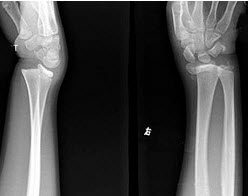

46、单项选择题

女,25岁,腕部疼痛,结合图像,最可能的诊断是()

A.肥大性骨关节病

B.骨髓炎

C.骨肉瘤

D.嗜酸性肉芽肿

E.骨膜下出血